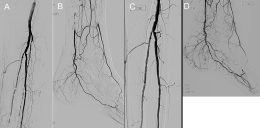

Critical limb ischemia is ischemic rest pain and / or nonhealing wounds of the lower extremity due to reduced arterial perfusion (1). Patients with critical limb ischemia are at elevated risk for amputation (2). Revascularization is an accepted treatment for patients with critical limb ischemia, when the goal is limb salvage, to improve perfusion and wound healing. Traditionally, restoring in-line flow to the foot via any tibioperoneal artery was thought to be sufficient for wound healing. However, more recently, there has been interest in pursuing revascularization of particular tibioperoneal and pedal arteries, depending on the vessel’s relationship to the wound (Figure – Click to enlarge). That is, target vessel revascularization is based on the ‘angiosome concept’.

The figure is from a case of an 85 year-old man with nonhealing, left heel wound for 6 months. The wound was located on the medial plantar surface of the heel. After the procedure wound healing was achieved.